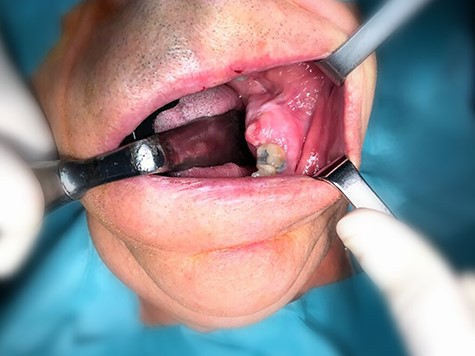

A 79-year-old man came to our department complaining of a painless swelling in the posterior region of the mandible, with uncertain beginning. The mandible in the left molar region was expanded to the buccal and lingual sides (Fig. 1). No fluctuation of the mandible or hypoesthesia of the lower lip was detected.

An incisional biopsy of the lesion revealed the presence of spindle cells and collagen bundle without atypical or mitotic figures, with a diagnosis of a transitional extracranial meningioma, similar to that of the frontal meningioma. The tumour, including the second molar, was completed removed from the mandible under general anaesthesia. After 6 months, the patient had no evidence of relapse.